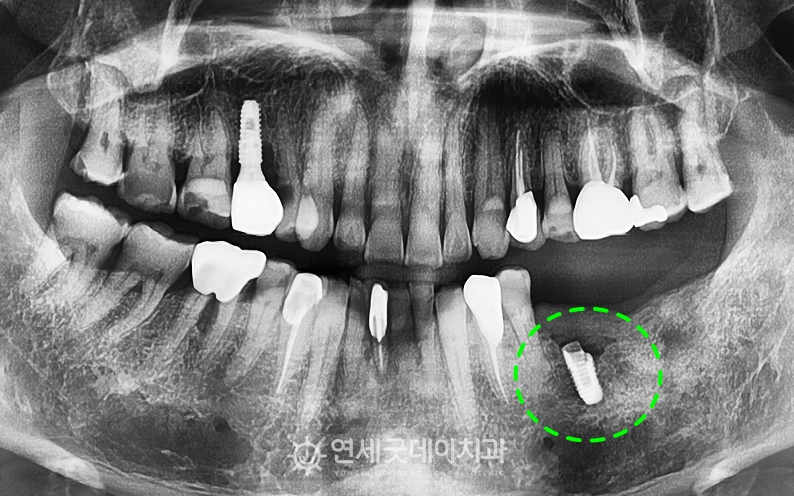

임플란트 재수술(i-Reset) 치료전후, 60대 남성

타원에서 치료 받으셨던 #36 부위의 픽스쳐 파절과

3D 프로그램을 이용해 임플란트와 하치조신경관의 환자분의 경우 임플란트 하단부와 하치조신경관 사이의

제거하기 위험한 케이스였음에도 CT분석을 통해

타원 임플란트를 제거한 부위는 무엇보다 하치조신경관과 가까워 위험도가 긴 치료 받으시느라 고생 많으셨습니다. ^^ ※ 모든 사진은 본인의 동의를 얻어 동일조건에서 촬영하였으며 |